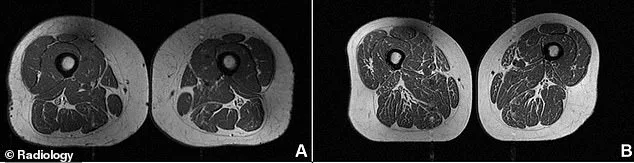

New clinical imagery provides a disturbing look at the internal damage caused by ultra-processed foods. Recent medical documentation reveals a woman's thigh cross-section that looks like a slab of marbled steak. This individual derived 87 percent of her nutrition from industrial formulations, including refined sugars, oils, and starches. These foods also contain additives like artificial flavors, colors, emulsified fats, and preservatives. Her diet consisted largely of regular soda, chocolate candy bars, and various cold breakfast cereals. Despite maintaining a moderate activity level, the high concentration of additives caused significant muscle marbling.

This condition, known as myosteatosis, occurs when fat accumulates directly inside the muscle fibers. A separate study involving 615 adults at risk for knee osteoarthritis revealed similar nutritional trends. These participants averaged a daily diet containing approximately 41 percent ultra-processed foods. Researchers found that higher consumption levels were directly linked to greater fat infiltration within muscles. This hidden fat replaces healthy tissue, which effectively weakens the body's primary locomotive structures.

Furthermore, these physiological changes are linked to metabolic syndrome and increased chronic inflammation. Patients with these muscle changes face higher risks of hospitalization and serious surgical complications. The danger is particularly acute for individuals already battling kidney disease, liver disease, or cancer. MRI comparisons highlight the disparity between a 30 percent UPF diet and an 87 percent diet.